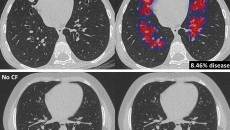

The new algorithm allows for automated analysis of CT scans of patients with the condition.